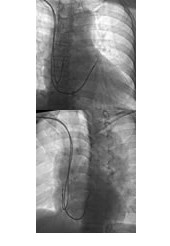

X线影像确定电极置入位置 前后位(AP)和右前斜位(RAO)可以判断电极位置在流出道的高位还是低位,左前斜位(LAO 30°~45°)则可判断电极位置在游离壁还是间隔部,若位于间隔部,电极头端指向脊柱(图2)。

图2 X线确定电极置入位置

A图为前后位(AP),可见电极位于流出道高位,B图为左前斜位(LAO 30°),可见心室导线头端指向脊柱。因此,此心室电极位置为右心室流出道高位间隔部。